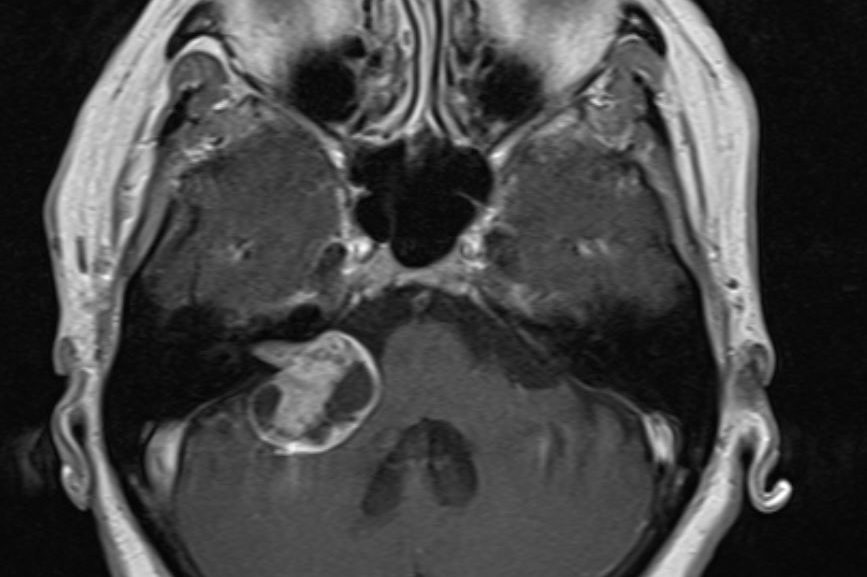

Ασθενής 19 ετών με γνωστή χωροκατακτητική εξεργασία (επιδερμοειδες γεφυροπαρεγκεφαλιδικής γωνίας δεξιά) με προοδευτικά σημαντική αύξηση μεγέθους. Νευρολογικά ακέραιος. Ο απεικονιστικός…